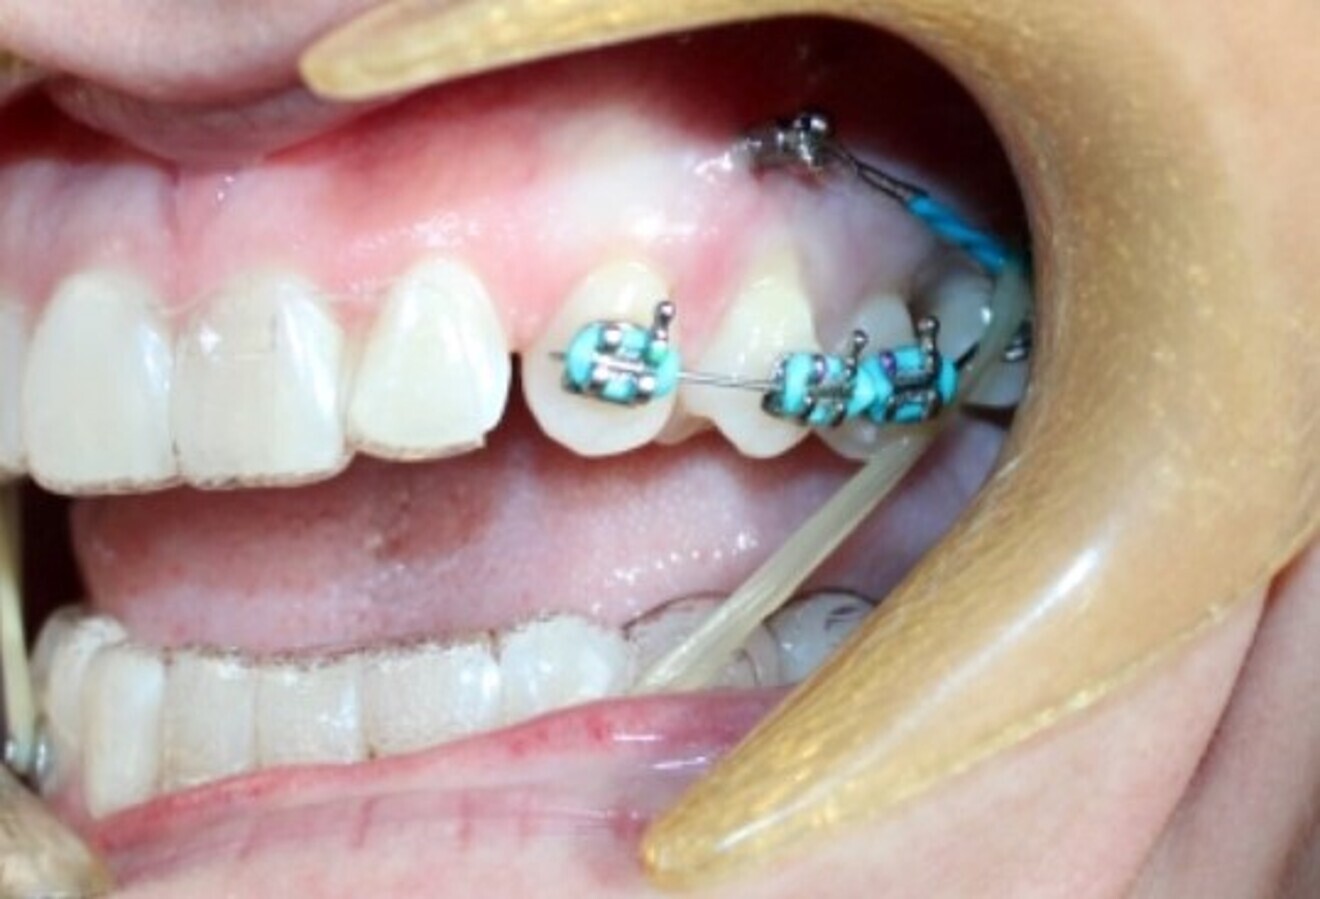

Class III antero-posterior corrections

Aligners alone will fail because there are often significant skeletal components to Class III malocclusion, along with dental compensations, frequently making Class III a very difficult malocclusion to address with aligners alone. Instead use fixed Class III correctors off mandibular canines or first premolars, extending back to mandibular first molars or second molars, for a more assured, fast and profound Class III correction as the maxillary arch is aligning with clear aligners. An example of such a device is the Carriere Motion 3D Class III appliance (Figs. 20–22). The outcome is Class III correction that is much more predictable than with clear aligners alone.

Fig. 21: Carriere Motion Class III appliance in place.